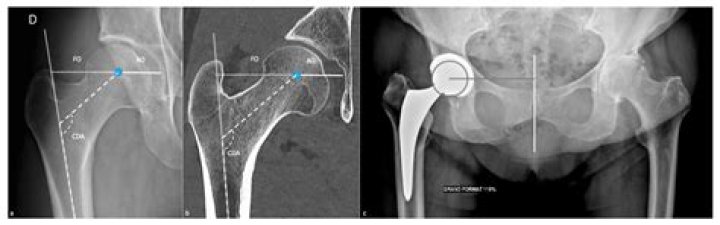

The femoral head is the most proximal portion of the femur and is supported by the femoral neck. It articulates with the acetabulum of the pelvis. The femoral head is nearly spherical (two-thirds) but has a medial depression known as the fovea capitis femoris that serves as an attachment point for the ligamentum teres.

The hip joint (see the image below) is a ball-and-socket synovial joint: the ball is the femoral head, and the socket is the acetabulum. The hip joint is the articulation of the pelvis with the femur, which connects the axial skeleton with the lower extremity.

How big is a femoral head?

The natural size of the femoral head usually ranges from 40 to 54 mm, with smaller sizes usually found in females. In the initial development of hip arthroplasty, artificial femoral heads were designed to replicate these anatomical dimensions.